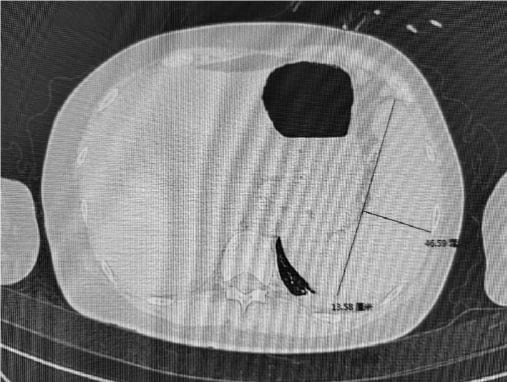

腹部CT提示脾脏增大(该病例脾长径约13.58 cm、厚径约46.56 mm)。